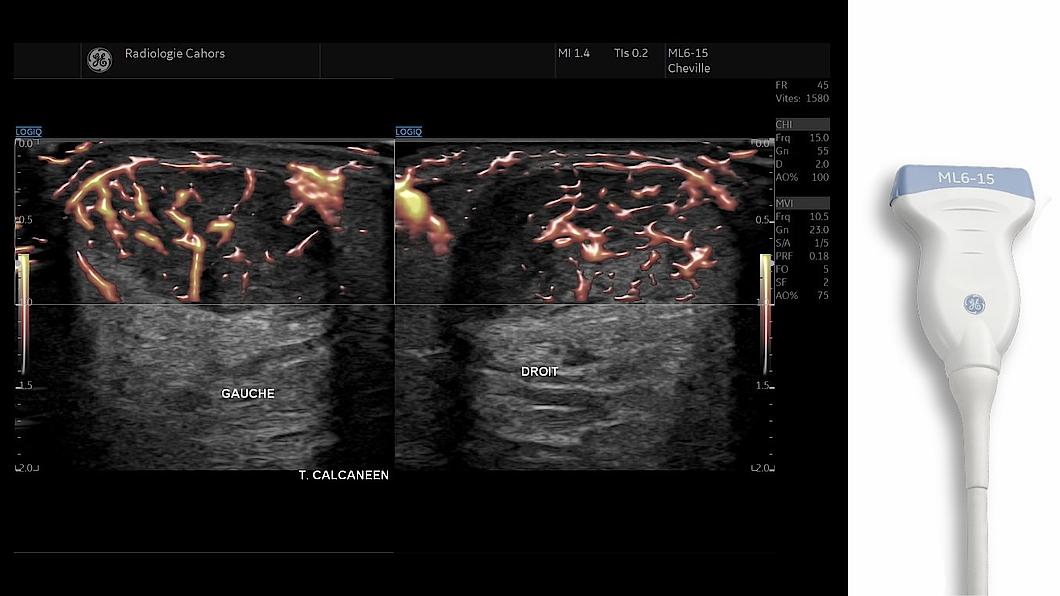

La quantification des pathologies inflammatoires repose sur des outils sensibles et reproductibles tels que le MVI ou le Compare assistant.

MVI

Micro Vascular Imaging : Ce mode de micro-vascularisation, une détection et une caractérisation plus fiable de celles-ci pour mieux évaluer les pathologies inflammatoires.

Sondes ML6-15

Une sonde échographique est un dispositif d'image échographique fixé à la console d'un système d'échographie et utilisé à des fins de diagnostic, notamment pour la réalisation de mesures sur l'image acquise. Ce dispositif est destiné à être utilisé par des médecins qualifiés et des échographistes professionnels disposant de connaissances élémentaires en matière d'échographie